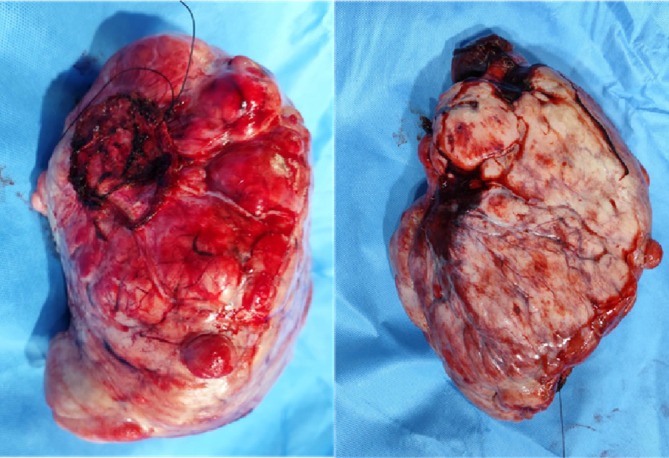

孤立性纤维性肿瘤(SFTs)是罕见的梭形细胞肿瘤,主要是良性的,占所有软组织肿块的不到2%。在极少数情况下,SFTs可导致doge - potter综合征,这是一种副肿瘤疾病,其特征是由于胰岛素样生长因子II (IGF-II)水平升高而导致低血糖。患者通常表现为与这种激素失调有关的症状性低血糖。我们报告一例70岁的男性,他表现为体重减轻,咳嗽,疲劳,刺痛,以及与复发性低血糖相关的精神错乱发作。胸片示右下半胸一大块软组织肿块,ct引导下活检证实右下叶基底段肿瘤浸润。

Solitary fibrous tumours (SFTs) are rare spindle cell neoplasms, predominantly benign, comprising less than 2% of all soft tissue masses. In rare cases, SFTs can lead to Doege-Potter syndrome, a paraneoplastic condition characterised by hypoglycaemia due to elevated levels of insulin-like growth factor II (IGF-II). Patients typically present with symptomatic hypoglycaemia related to this hormonal dysregulation. We report the case of a 70-year-old man who presented with weight loss, cough, fatigue, tingling, and episodes of confusion associated with recurrent hypoglycaemia. Chest radiography revealed a large soft tissue mass in the right lower hemithorax, and CT-guided biopsy confirmed tumour infiltration in the basal segment of the right lower lobe.